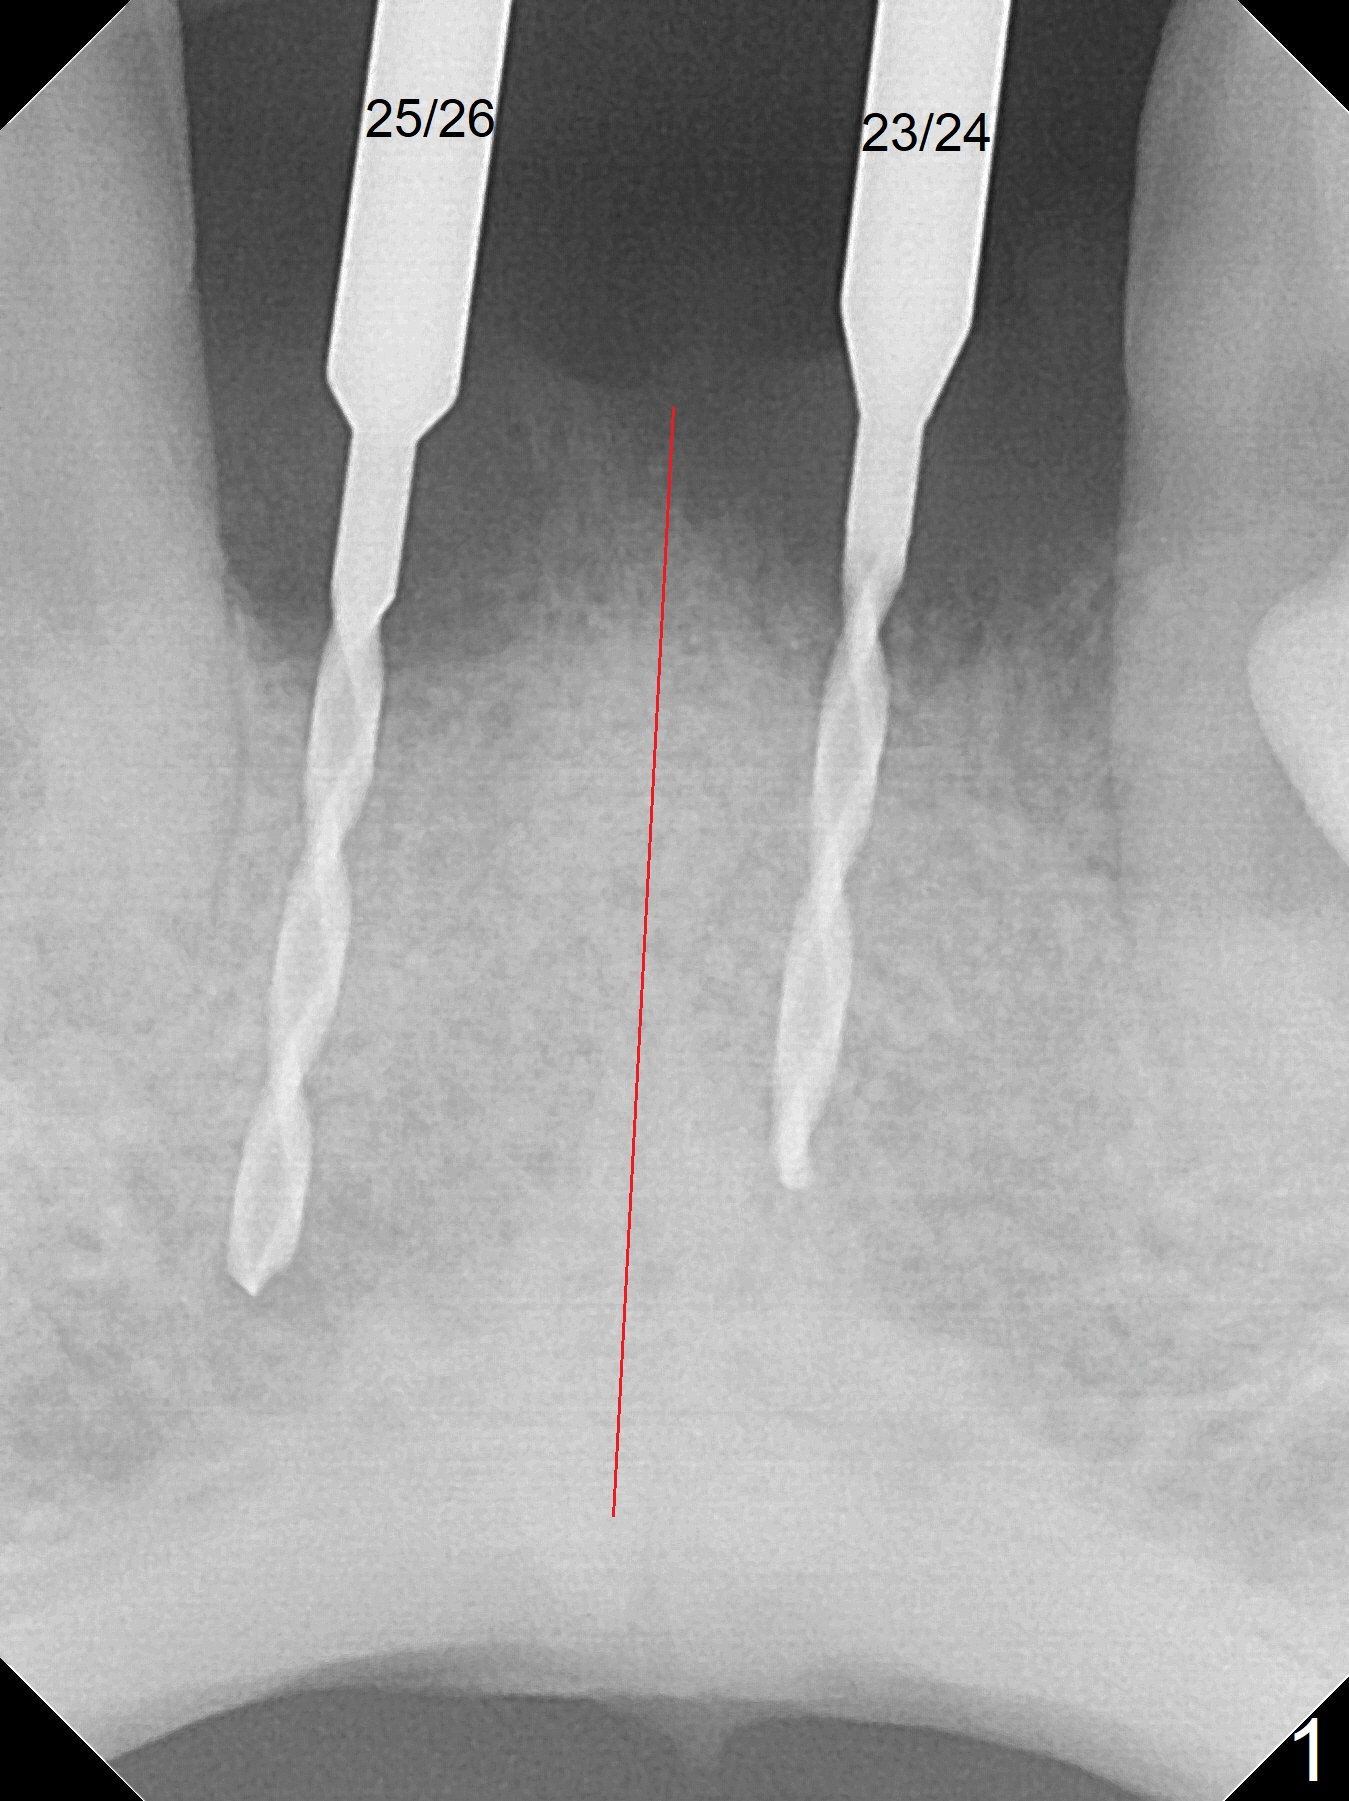

After extraction of 4 of the lower incisors, there are basically 2 sockets (#23/24 and 25/26), separated by the apparently midline bone (Fig.1 red line). In spite of using Lindamann bur to move the 25/26 osteotomy mesially, a 3x14(2) mm dummy implant remains close to the tooth #27 (Fig.2). The terminal branch of the Incisive Canal (<) is located between the lateral and central incisors. A de novo osteotomy (Fig.3 (1.5 mm drill)) is made mesial to the original one (O). While the 3x14(2) mm dummy implant is incompletely placed at #25/26, a 3x14(4) mm 1-piece one is placed at #23/24 (Fig.4). Finally the same implant is placed at #25/26 with placement of mineralized cortical/cancellous bone (Fig.5 *). When the large sockets are sutured, the supraerupted teeth #7-9 touch the lower gingiva (Fig.6). The incisal edge is reduced for clearance (Fig.7). Periodontal dressing is less likely to be dislodged with the incisal edge reduction (Fig.8,9). A provisional FPD is fabricated 1 week postop. Hard (Fig.10) and soft (Fig.11,12) tissues heal 5.5 months postop. The patient returns for crown cementation 3 months post impression (9 months postop, Fig.13,14).